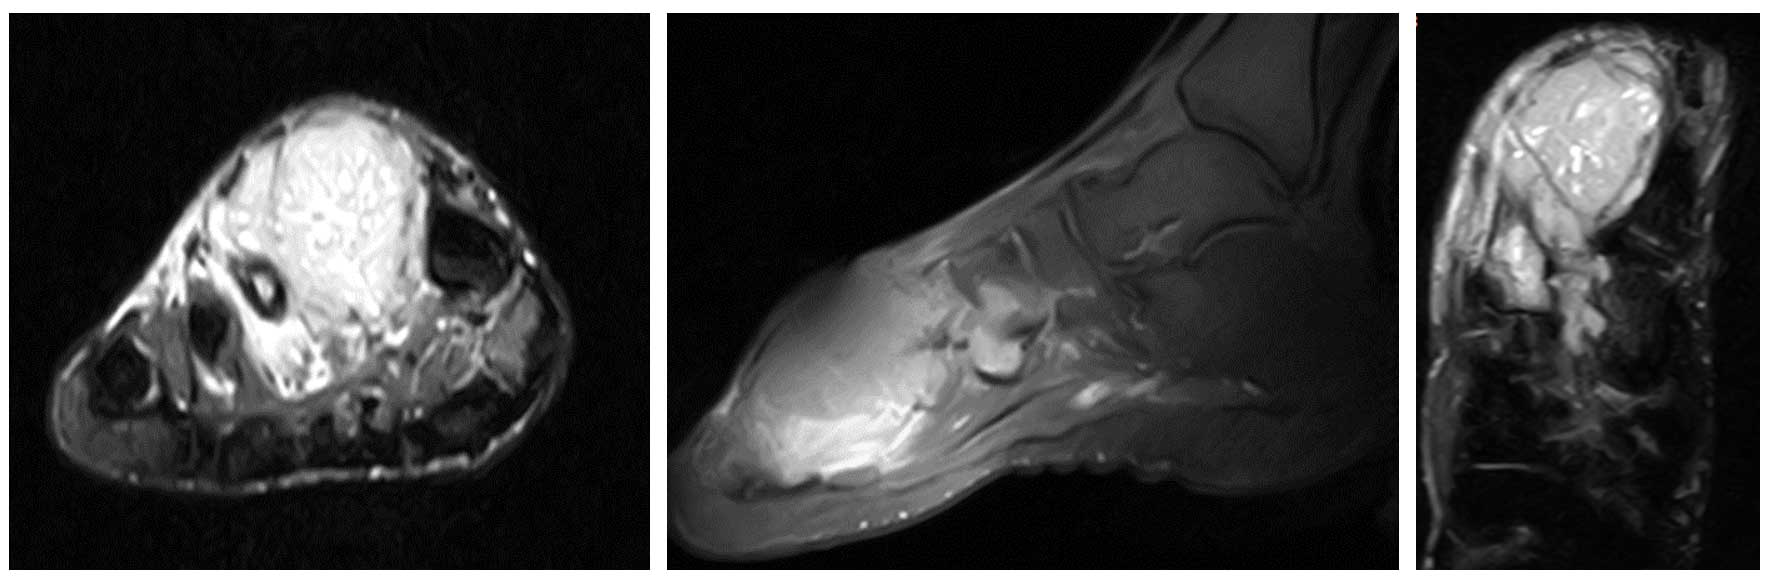

Ameliyat Öncesi: MR’da 2. metatarsı çepeçevre saran düzensiz sınırlı ve heterojen kitle görülmekte.